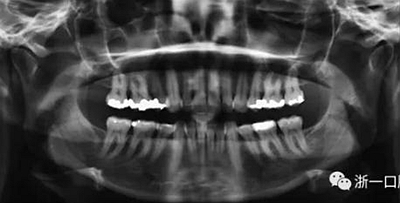

患者曾行正畸治療,現(xiàn)覺(jué)笑容不美觀前來(lái)就診。患者正面觀及側(cè)貌示下頜發(fā)育不足,偏高角,唇閉合不全。上下頜中線齊。覆合、覆蓋4毫米。磨牙關(guān)系及尖牙關(guān)系II類(lèi)。上頜擁擠度4mm,下頜擁擠度6mm。4顆第一前磨牙在第一次正畸治療時(shí)已拔除。上下牙弓呈尖圓型,牙弓狹窄。

頭影測(cè)量分析,SNA角84°,ANB角6°,高角型,詳見(jiàn)下表。

由于下頜中切牙間沒(méi)有間隙行下頜正中切開(kāi)術(shù),故進(jìn)行術(shù)前正畸擴(kuò)展間隙。下頜前牙粘托槽,中切牙托槽成交放置,將中切牙牙根分開(kāi)。使用0.018X0.018鎳鈦絲及置于下頜左、右中切牙之間的推簧推間隙。3個(gè)月后拍攝CBCT示已有足夠間隙行下頜正中截骨術(shù)。

全麻下進(jìn)行上頜骨腭中縫骨皮質(zhì)劈開(kāi)及下頜正中劈開(kāi)術(shù)。手術(shù)后,用X光片檢查上頜骨和下頜骨中線切口的位置和方向。

擴(kuò)弓保持8周后,除擴(kuò)弓器影響牙外粘接托槽,使用0.014鎳鈦絲進(jìn)行排齊、整平。旋轉(zhuǎn)停止后3個(gè)月拆除擴(kuò)弓器,全口粘接托槽,使用0.016niti繼續(xù)排齊整平。佩戴可摘保持器,保持上頜寬度。在使用至0.018x0.018niti7周,徹底排齊整平后,使用大弓型的0.016x0.022不銹鋼絲,繼續(xù)維持原有寬度,同時(shí)停止使用可摘保持器。掛II類(lèi)牽,糾正磨牙關(guān)系,使用鏈圈關(guān)閉散在間隙,少量使用IPR去除局部前牙的黑三角。術(shù)后9個(gè)月拍全景示,牙根平行度可,再無(wú)其他牙根出現(xiàn)問(wèn)題。1年7個(gè)月后治療結(jié)束。上下頜3-3舌側(cè)保持器+哈雷氏保持器進(jìn)行保持。